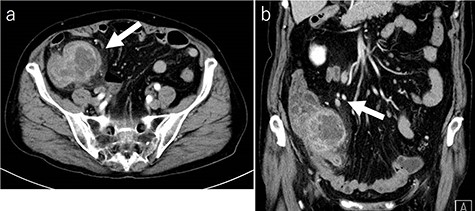

Laboratory tests revealed that her white blood cell count and carcinoembryonic antigen (CEA) levels were within normal limits (8600/μl and 2.4 ng/ml, respectively). However, C-reactive protein and carbohydrate antigen 19–9 (CA 19–9) levels were elevated (17.73 mg/dl and 87.8 U/ml, respectively). Colonoscopy showed swelling of the Bauhin valve and an elevated tumor of the terminal ileum (Fig. 1), but the biopsy specimen showed no malignancy. Abdominal contrast-enhanced CT detected a partially high-density tumor (diameter: 90 × 70 mm) in the cecum with some peripheral lymphadenopathy (Fig. 2). Magnetic resonance imaging (MRI) revealed a tumor (diameter: 60 × 40 mm) with thickening of the appendix wall near the cecum (Fig. 3). Although her pain resolved with conservative therapy, we diagnosed as suspected cecal cancer based on the imaging findings and elevated tumor marker levels.

MRI findings (a: T2-weighted axial image; b: contrast enhanced T1-weighed coronal image). MRI showing a tumor (diameter: 60 × 40 mm) with thickening of the appendix wall near the cecum (arrow).